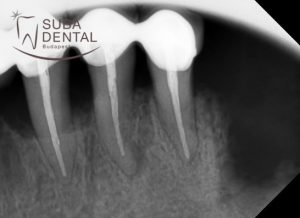

The dark shadow around the implants (peri-implantitis) in the intraoral X-ray scans.

Bone resorption around the teeth, periodontal pockets and inflammation in the intraoral X-ray scans.